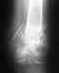

у меня перелом малой берцовой кости левой ноги , два месяца проходил в гипсе и ещё месяц без гипса но кость так и не сростается , хирург говорит что ногу надо держать в покое , травмотолог напротив ,что на ногу надо потихоньку давать нагрузку до 80 % , Нога не болит и практически не беспокоит , немного припухшая , Каждый день ем творог , пью кальций, месяц употреблял " Остеогенон" , Также хожу на физиотерапию , почему нога так и не сростается ?

Именно этим я сегодня и занимался , Был на приёме у зав. отделением травмотологии ( именно там где делают операции ) Дело в том что гипс вообще был не нужен достаточно было пару недель походить с палочкой, кость именно от этого и не срастается что на неё не даётся нагрузка и кровь застаивается Мне объяснили что даже когда ломают и большую и малую кость в основном лечат только большую а на малую и внимания не обращают , мне сказали что бы я оставил кастыли и ходил без них в крайнем случае с палкой.